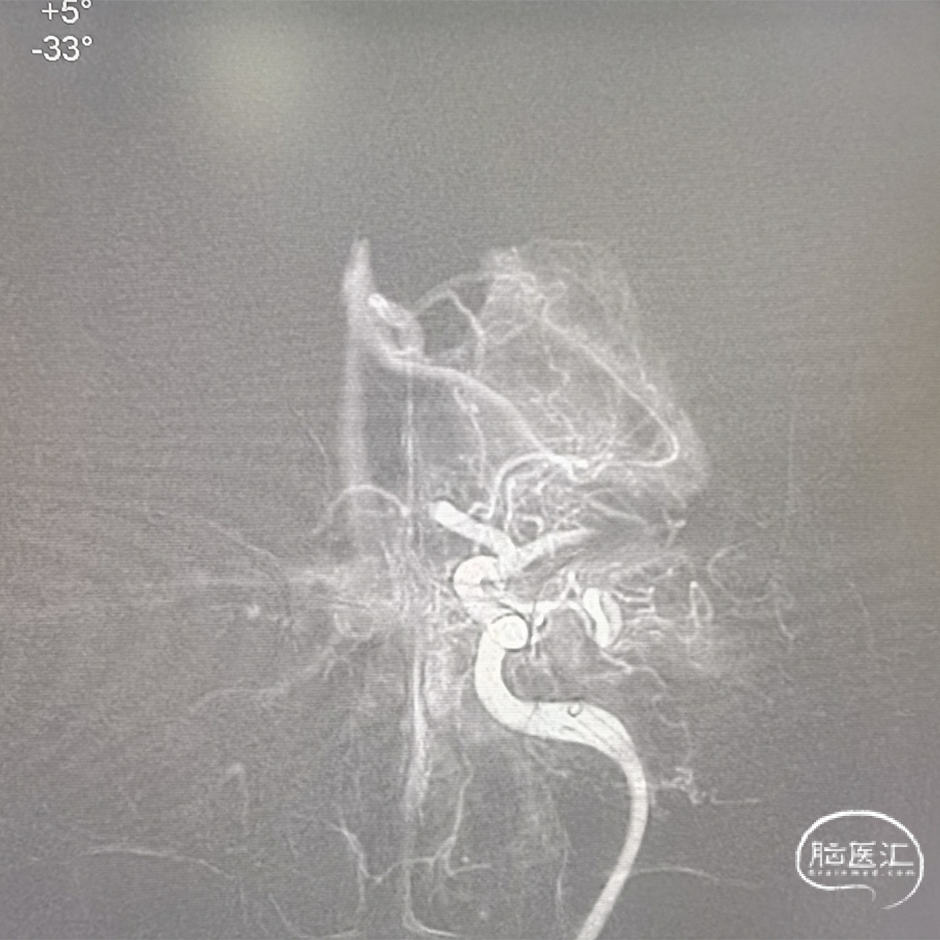

右侧颈总正侧位:见右侧颈内动脉闭塞,颅外血管代偿良好。

左椎正侧位:椎基底动脉未见异常,可见部分代偿。

左颈总正侧位:左侧颈内动脉闭塞,可见血管残端。

6F 115cm中间导管抽吸血栓2次后路图,见大脑中动脉、大脑前动脉闭塞。

大脑前动脉第一次取栓后路图,血管仍闭塞,且长鞘掉到颈总。